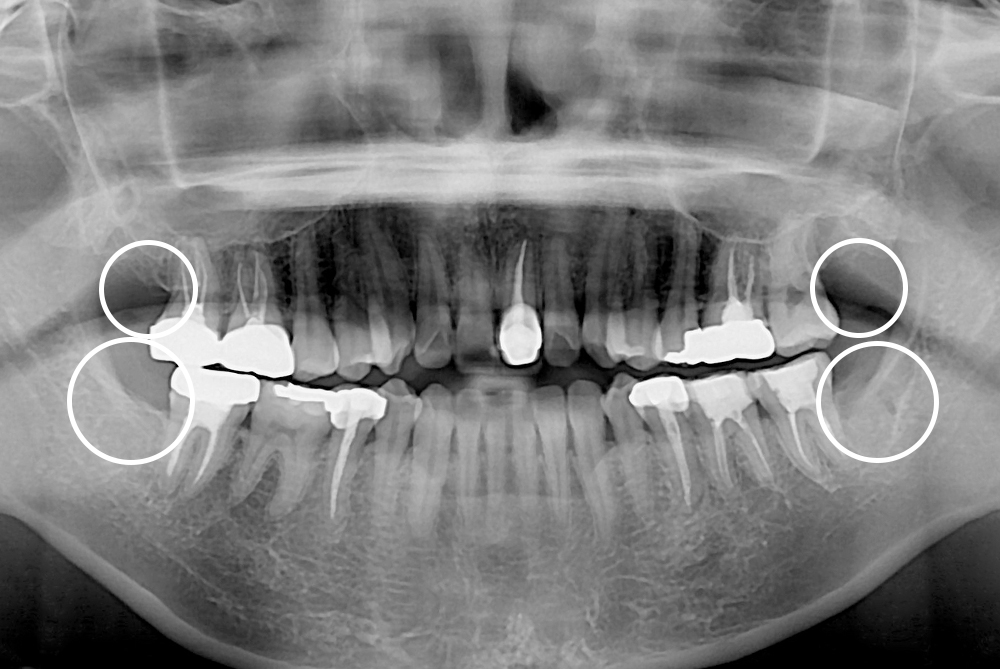

[사랑니] 매복 사랑니 발치

치료후 : 2019-11-20

세종치과는 구강악안면외과학 박사이신 원장님이 발치하는 치과입니다.